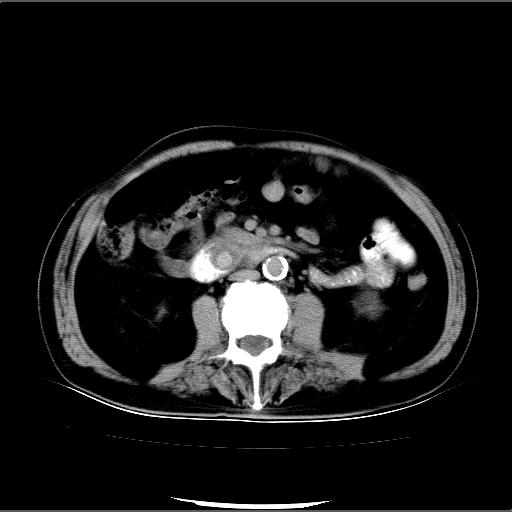

患者男82岁,黄染,发热10天,无腹痛。

1胆总管下端结石伴肝内外胆管扩张;2胆囊颈部结石伴胆囊积液

胆囊多发结石,胆囊积液;胆总管中下段结石,中上段扩张。

胆总管下段结石伴胆道系统扩张;胆囊炎伴胆囊结石.

1、胆总管壶腹部结石并胆总管、胆囊及肝内胆管扩张。2、胆囊多发结石。3、两下胸膜局限性增厚。4、胃体部大弯侧胃壁稍厚,建议:多量饮水后增强ct扫描除外占位性病变。

此病例有结果了:患者术后为:胆总管下段结石伴胆道系统扩张;胆囊炎伴胆囊结石。

各位战友分析的都很正确,是一个典型的病例。